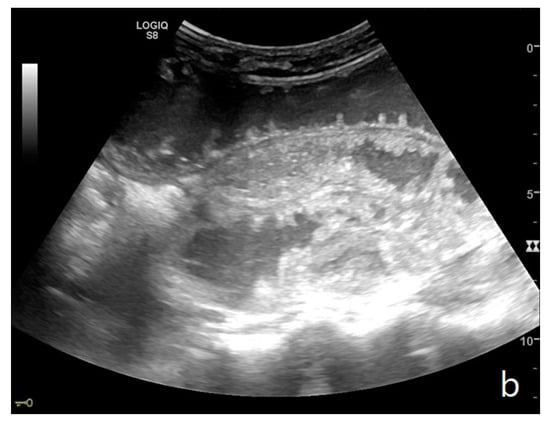

Figure 4.

A complicated SBO in a 69-year-old male with gastric cancer and peritoneal carcinosis. Ultrasound images show long (a) and axial (b) evaluations of a fluid-filled, dilated small bowel loop with hyperechogenic floating material (shown with an asterisk) (b,d). Bowel peristalsis was absent. Mild parietal and valvulae conniventes thickening are present (c,d). Downstream loops present normal caliber (bowel jump diameter). Free fluid is interposed between bowel loops (black arrow) (b).

The valvulae conniventes (Kerckring valves, circular folds) are permanent folds composed of mucosa and submucosa that project into the intestinal lumen and are clearly visible in the case of fluid distension (keyboard sign) [31]. At an early stage of SBO, it is not uncommon to see the valvulae in the upstream loop appearing more numerous and closer to each other. As the occlusive state continues, the loop upstream of the obstructive fulcrum becomes weaker, bowel walls appear thin, and the folds flatten (Figure 2a and Figure 3a,b). The upstream loops more distant from the obstructive fulcrum may still present peristalsis, albeit reduced and ineffective. In complicated ileus, with the onset of vascular loop distress, the walls and valvulae become thicker and weaker due to parietal edema and venous stasis, with possible dramatic parietal necrosis and subsequent perforation (Figure 4a–d and Figure 5a,b) [12,43].